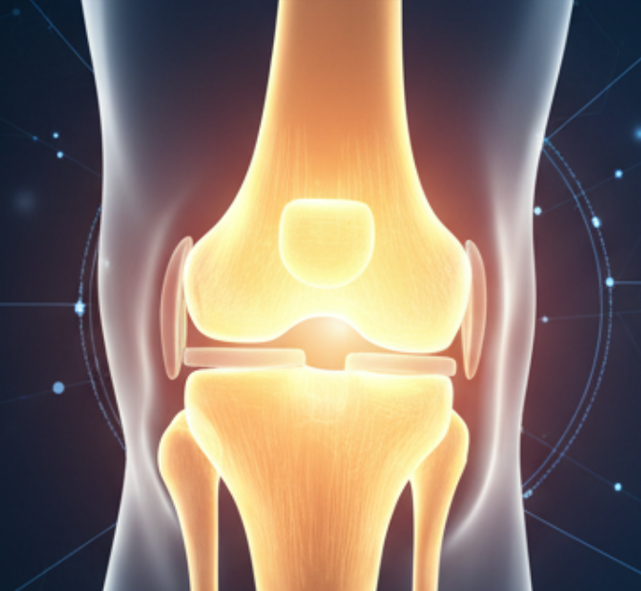

Knee

Anatomy

Runner’s Knee, also known as Patellofemoral Pain Syndrome, is a common condition that causes pain around or behind the kneecap. Despite its name, it doesn’t only affect runners; anyone engaging in repetitive knee-bending activities or daily movements can experience this condition.

- Maltracking of the Patella

When the kneecap moves improperly within its groove, it can irritate the cartilage and surrounding tissues, causing pain and inflammation.